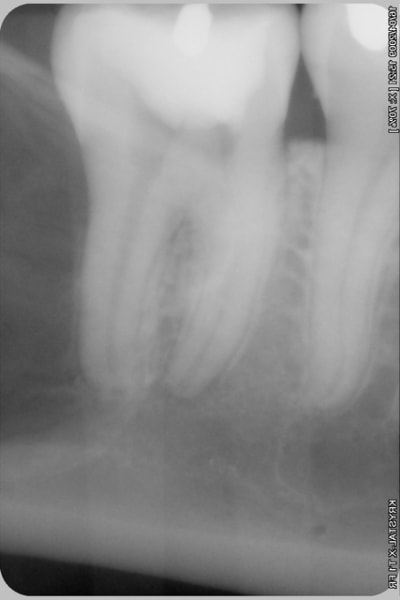

j'attends le resultat de l'irm

et ensuite ....

l'os est fin quand même, non?